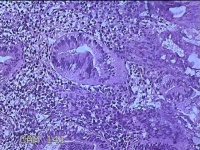

子宫腔赘生物

性别

女

年龄

33岁

临床诊断

子宫内膜息肉?子宫异常出血

一般病史

阴道流血12天。

标本名称

大体所见

灰白粉红色不规则肿物1.5x1.3x0.2cm一堆,表面糜烂。

图1